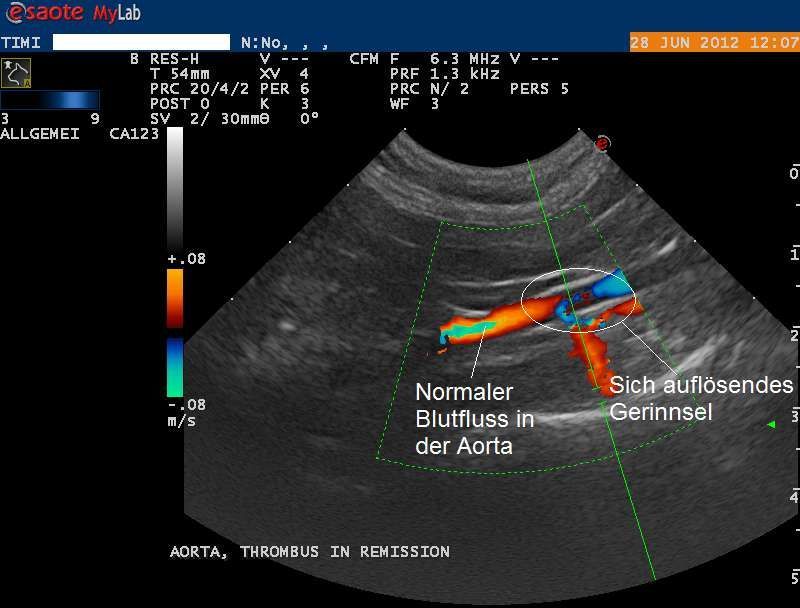

Nun wird die Körperschlagader mittels Ultraschall genauer untersucht. Diese zweigt sich vor dem Beckeneingang unter anderem in die beiden Schenkelarterien auf und versorgt so die Gewebe der Hinterbeine mit Sauerstoff. Eine Doppler-Ultraschalluntersuchung zeigt, dass die Körperschlagader nicht mehr komplett durchgängig ist und nur noch sehr wenig Blut die Beinarterien erreicht. Beim Doppler-Ultraschall kann fliessendes Blut farbcodiert dargestellt werden und so Hindernisse in einem Gefäss dokumentiert werden.

Im Lauf der nächsten Tage verbessert sich der Zustand von Timi zusehends. Der Schenkelpuls ist wieder an beiden Beinen spürbar und die Pfoten erwärmen sich zusehends. Eine weitere Ultraschalluntersuchung zeigt, dass die Körperschlagader in der Region des Verschlusses deutlich besser durchgängig ist.